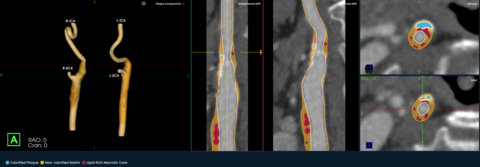

BOSTON--(BUSINESS WIRE)--Elucid, an AI medical technology company focused on providing physicians with a more precise view of atherosclerosis to drive patient-specific therapeutic decisions, announced the launch of its PlaqueIQTM image analysis software for the quantification and classification of plaque morphology in the carotid arteries. The first and only CT-based plaque analysis software indicated for the carotid vasculature, PlaqueIQ may help physicians diagnose carotid plaques at risk for rupture and develop patient-specific treatment pathways to prevent and monitor against ischemic stroke.

PlaqueIQ is the first and only FDA-cleared, non-invasive plaque analysis based on objective histology, offering physicians non-invasive CT Virtual Histology™. PlaqueIQ delivers quantification and classification of plaque morphology and is uniquely capable of identifying and quantifying lipid rich necrotic core, the plaque type strongly linked with both cardiovascular and cerebrovascular risk.2,3,4

PlaqueIQ is designed to help physicians prioritize and personalize treatment based on actual coronary and carotid artery disease, rather than population-based risk. The technology supports physicians in evaluating treatment of patients’ symptoms and risk of future events, such as heart attack and stroke, and enables the development of personalized care pathways informed by each patient’s individual plaque characteristics.

When used for both the coronary and carotid arteries, PlaqueIQ non-invasively delivers a quantitative and qualitative assessment of systemic atherosclerotic risk and creates the potential to perform both coronary and carotid plaque analysis in a single scan.